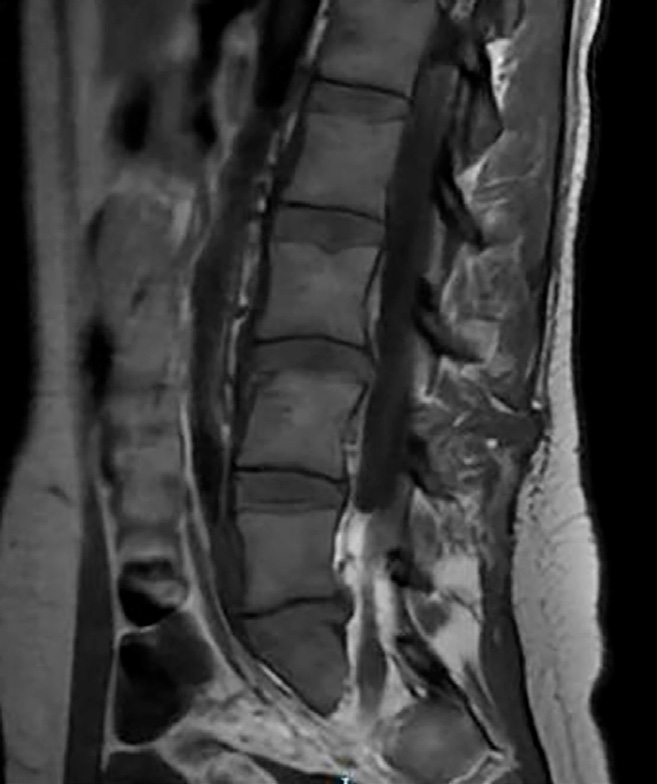

Se procede a realización de TC urgente donde destaca la presencia de contusión pulmonar, sin neumotórax, mínima cantidad de líquido libre periesplénico y fractura del cuerpo vertebral de L4 que involucra a su plataforma articular superior, sin pérdida de altura ni retropulsión hacia el canal medular, con posible foco de hematoma epidural. Adicionalmente, se realiza Rx de la muñeca afecta, donde se observa una fractura-luxación de Galeazzi.

Tras 9 días de ingreso y comentar el caso con el equipo de columna para indicaciones al alta de cara a una IQ definitiva de la muñeca de manera diferida, se decide solicitar una RMN donde se informa una extensión de la fractura hacia los elementos óseos posteriores y disrupción completa del complejo ligamentoso posterior de L3-L4. En base a los nuevos hallazgos, se opta por estabilización de la lesión mediante fusión posterior instrumentada de L4 y L5 con aporte de injerto óseo.

La fractura de chance combinada con lesión ligamentosa es una fractura infrecuente, pero seria, que se puede presentar tras un mecanismo de flexión-distracción al comprometer el cuerpo vertebral en el eje axial. Es fundamental una sospecha precoz, en especial tras dicho mecanismo lesional, ya que hasta el 30% de las lesiones se pasan por alto en la evaluación inicial, incluso tras la realización de un TAC convencional. Adicionalmente, estas lesiones presentan una alta asociación con daños intraabdominales, reportados en hasta el 50% de los casos, lo que denota su importancia. Con todo ello, la RMN es crucial para identificar lesiones del complejo ligamentoso, elemento que determinará el manejo definitivo. En casos con disrupción del citado complejo posterior, como este, está indicada la estabilización quirúrgica para garantizar la estabilidad de la columna y prevenir complicaciones futuras.